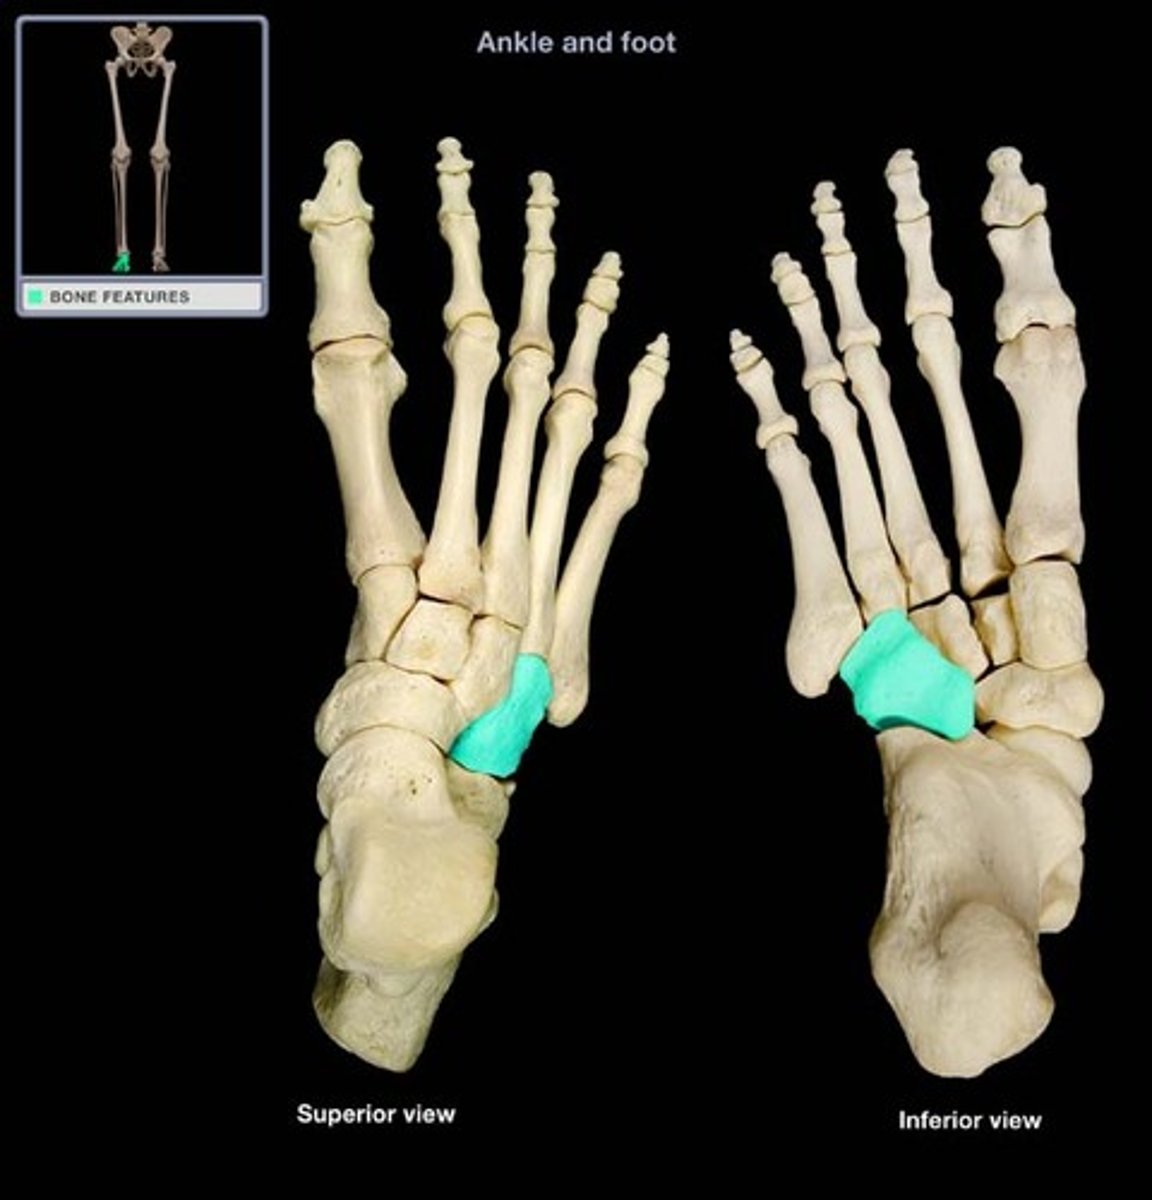

Navicular